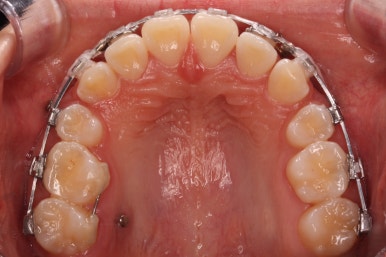

틈은 다 다물어졌고, 부가적인 정교한 마무리 과정을 더 거치게 됩니다.

중앙선도 잘 맞고 교합도 잘 마무리되었습니다.

이 뽑은 자리가 다시 벌어지지 않게 앞니가 다시 틀어지지 않게 유지철사를 부착하고 마무리를 하였습니다.

중앙선, 교합, 뻐드러짐 모두 좋아졌고 이를 뽑고 교정했지만 발치 공간이 남지 않고 잘 마무리 되었습니다.